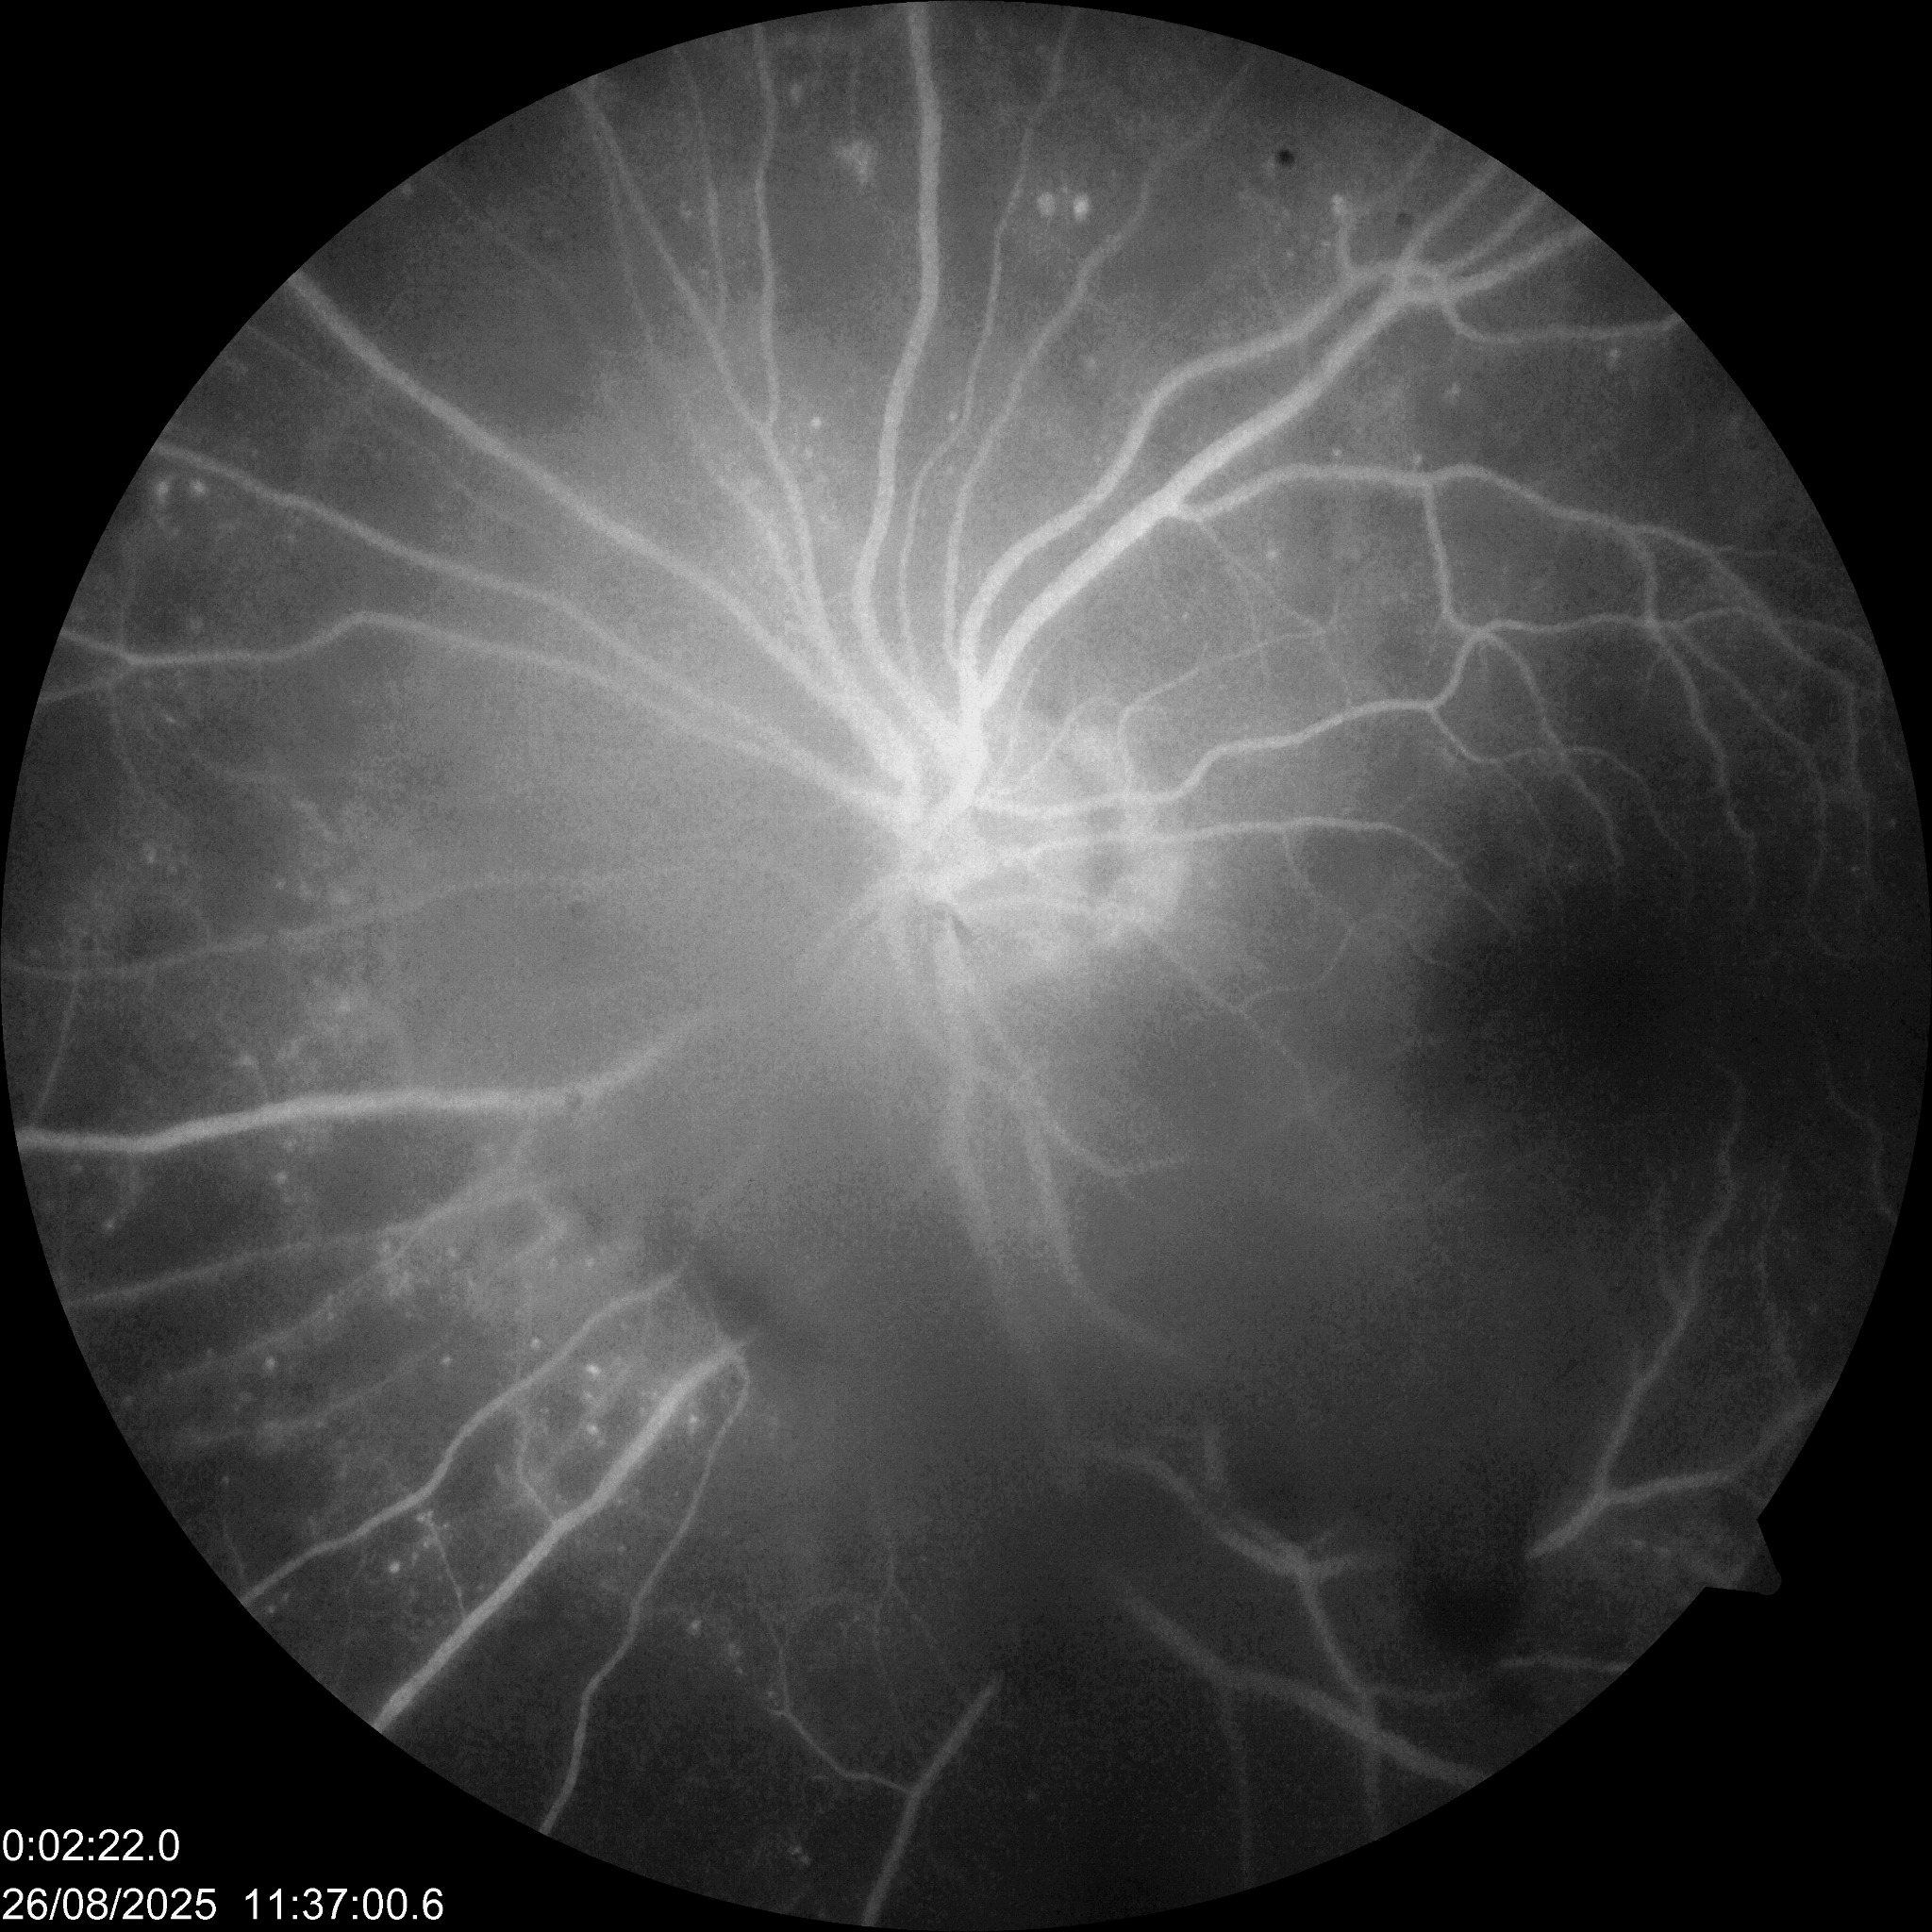

| RDP | ![]() | ![]() | Normal o EMD | Normal o engrosamiento coroideo | ![]() | LASER | Neovasos |

| RDP HV o HS | ![]() ![]() ![]() | ![]() ![]() ![]() | Normal o EMD | Normal o engrosamiento coroideo | ![]() | CIRUGIA: Vitrectomía + Endolaser | H Vítrea H Subhialoidea |